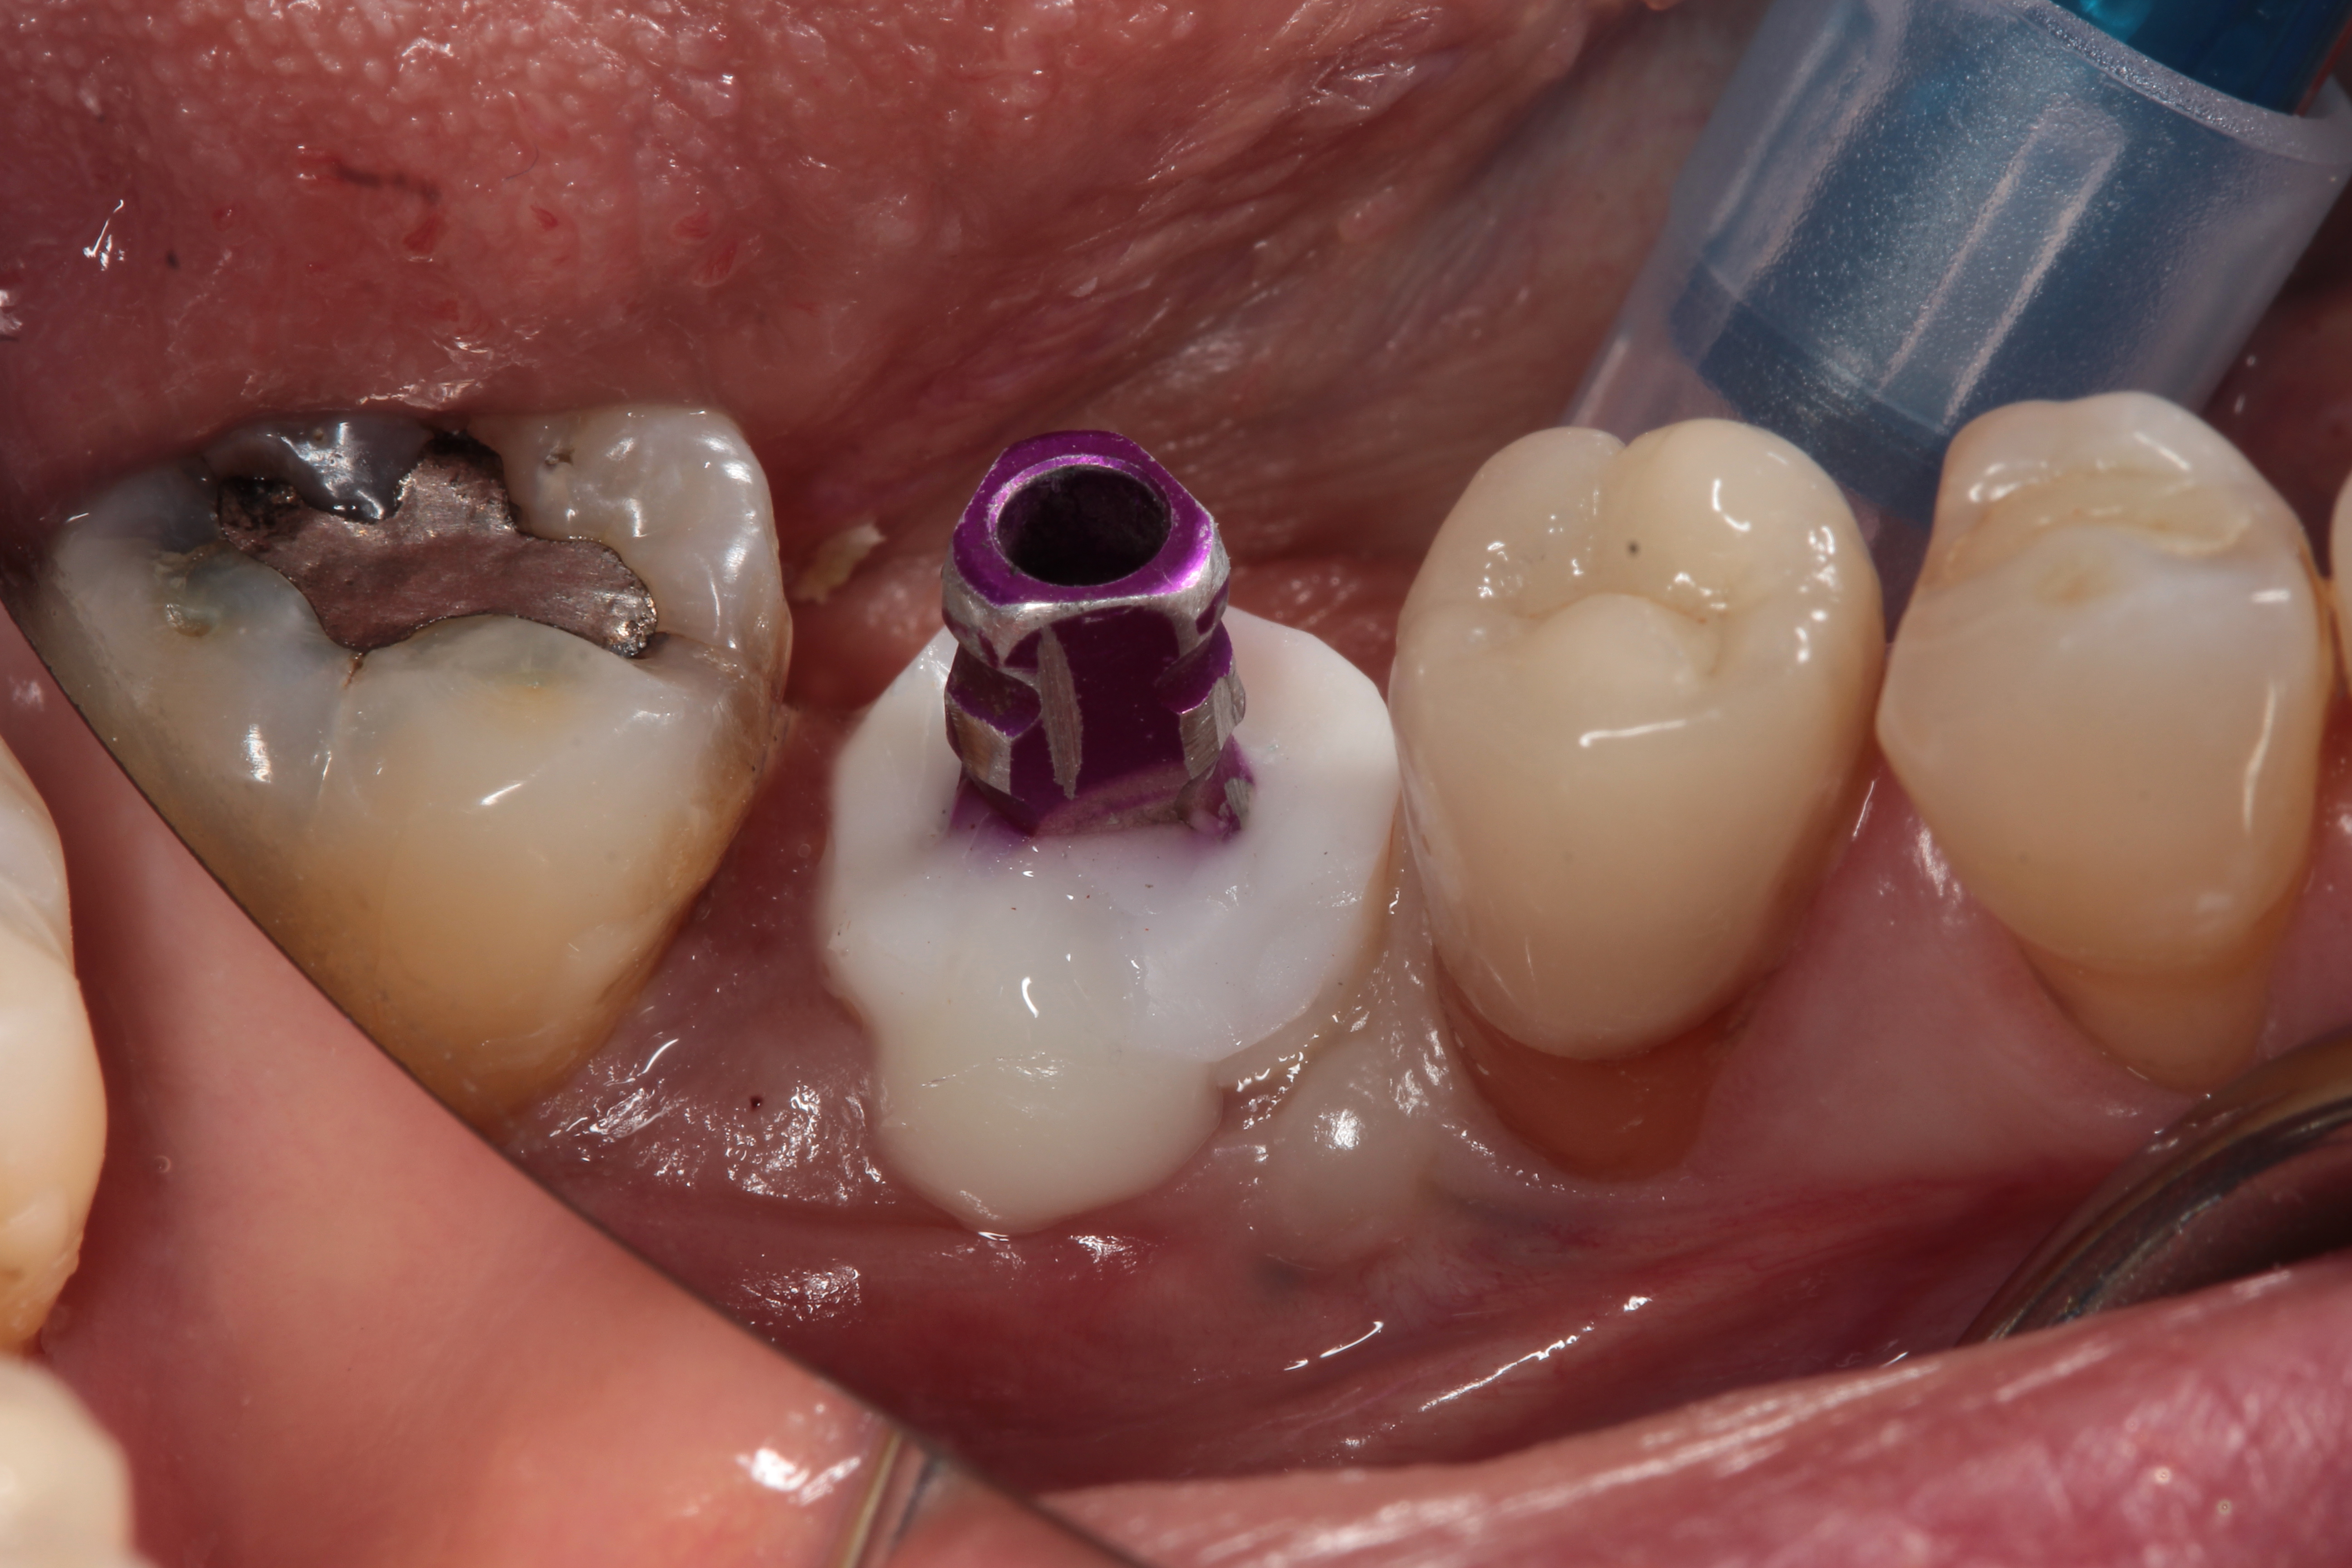

Fig 13. A custom healing abutment was created to replicate the emergence profile for a mandibular molar, which is square in cross-section.

Figure 13

A 4.8 mm x 10 mm implant (Straumann® Bone Level Tapered [BLT], Straumann) had been placed at the mandibular first molar site and was ready for restoration. A custom healing abutment was fabricated and inserted at the time of surgical implant placement and soft tissue was sutured around the abutment using 4/0 Glycolon sutures (Osteogenics Biomedical, osteogenics.com) (Figure 13). A periapical x-ray was taken at the time of placement of the custom healing abutment to confirm full seating (Figure 14).